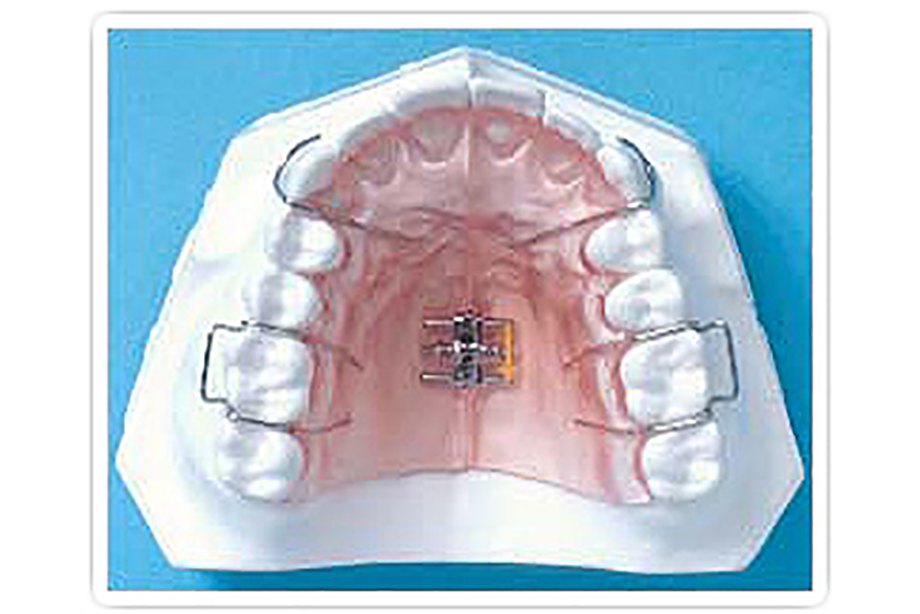

取り外し可能な

プレートタイプ

取り外さない

固定タイプ